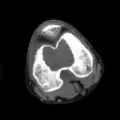

1. a. X-ray of chondroblastoma of thigh bone near knee

1. b. CT scan shows chondroblastoma of thigh bone near knee more clearly

1. c. CT scan of chondroblastoma of thigh bone near knee (cross-section view)